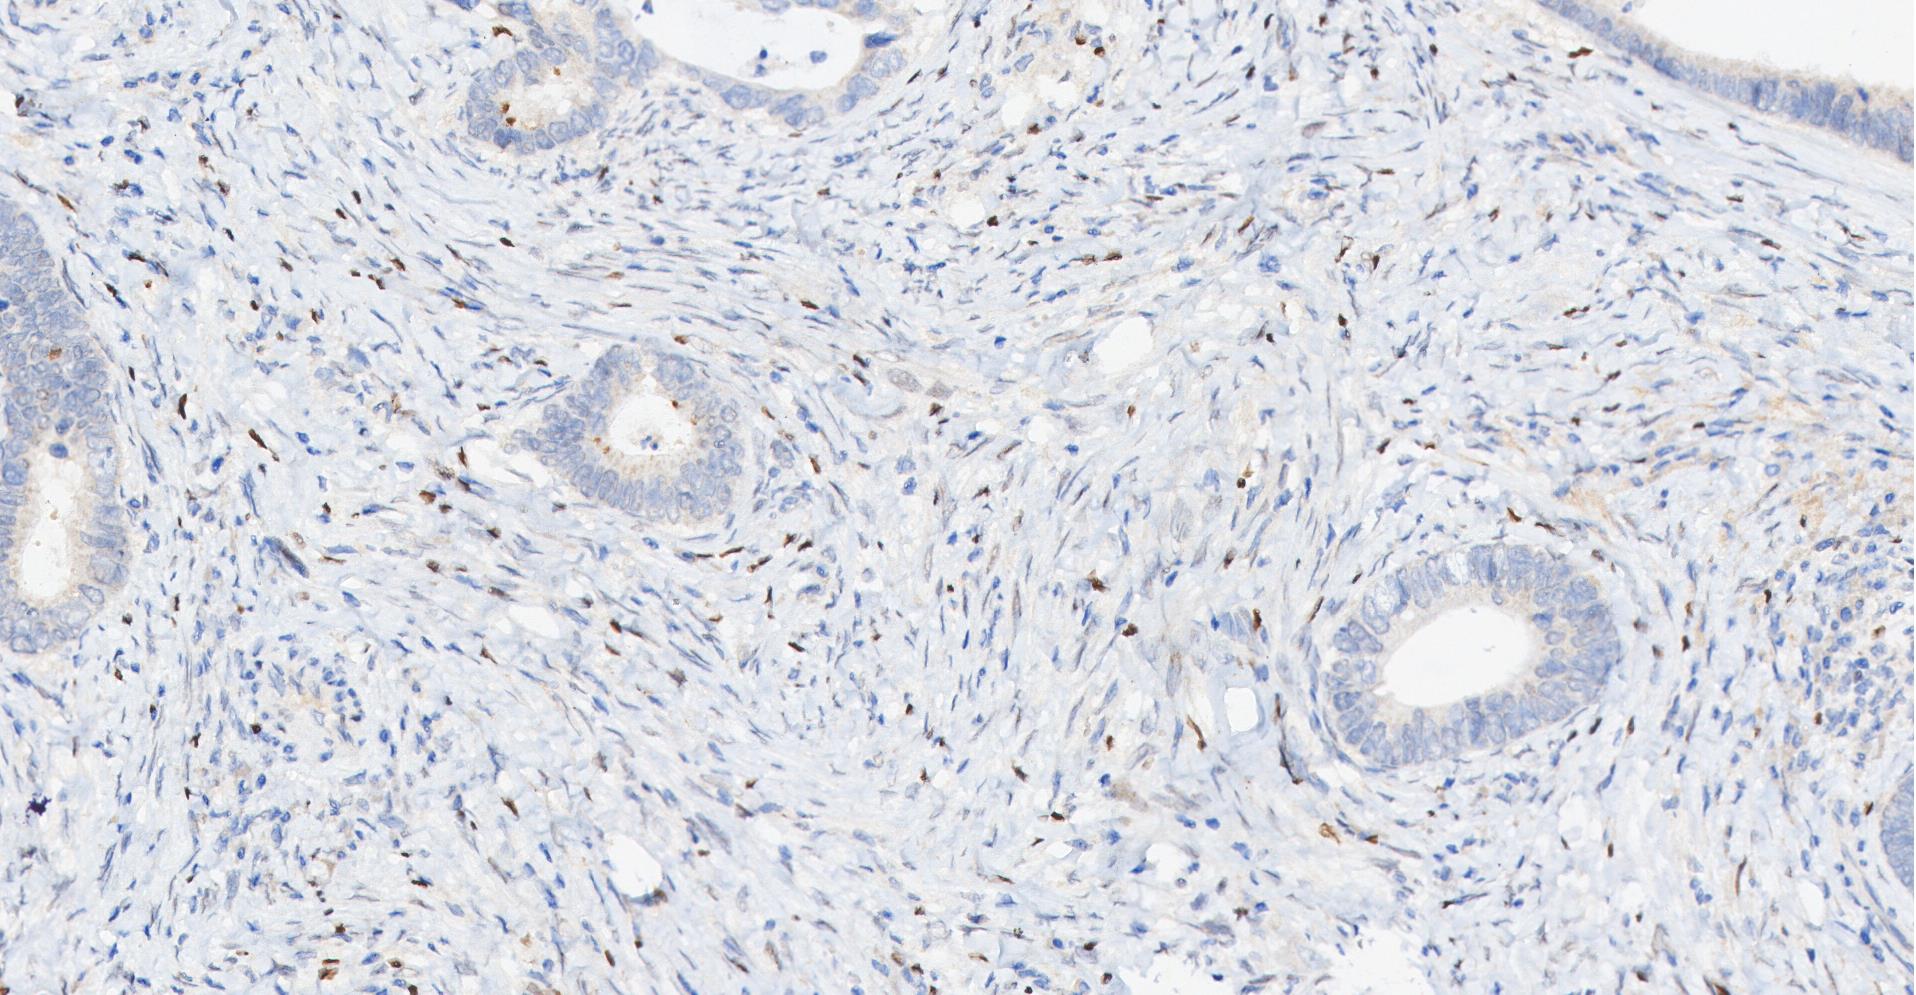

• Immunohistochemical analysis of paraffin-embedded human Colon cancer‌ tissue using FOXP3 antibody was performed. The section was pretreated using high-temperature and high-pressure mediated EDTA antigen retrieval buffer (pH 9.0), for 5 minutes. The tissues were incubated with primary antibody (HY-P80965, 1:100 dilution) at room temperature for 60 minutes. Detection was performed using an HRP conjugated compact polymer system. DAB was used as the chromogen. The tissues were counterstained with hematoxylin and mounted with neutral balsam mounting medium.